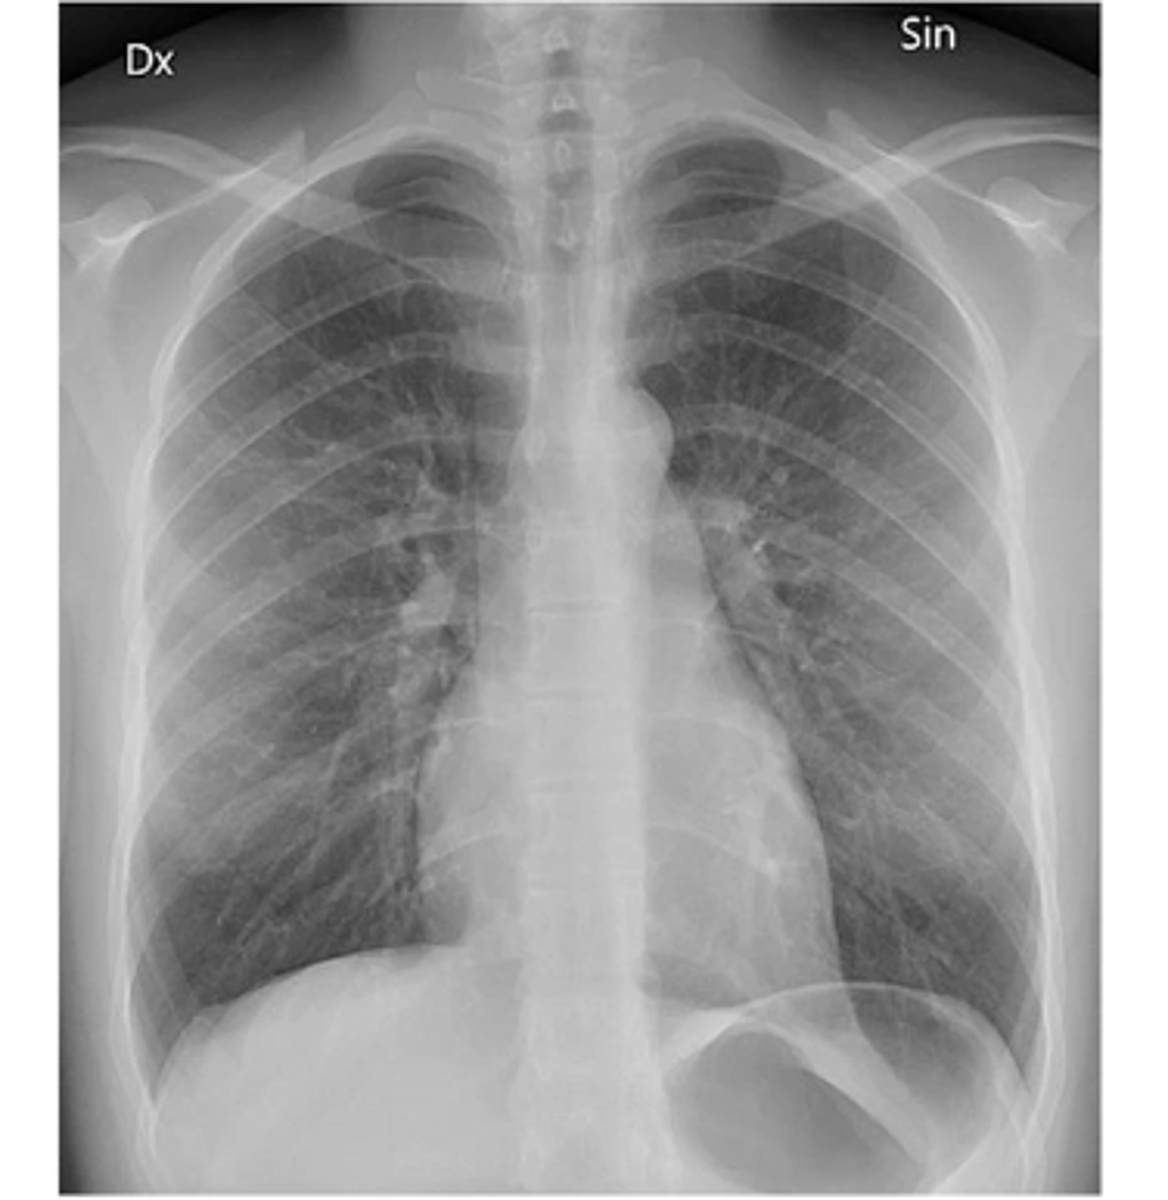

View: PA

Structure: chest

State the type of view and structure being depicted.

Chest x-ray

Q: a coast to coast flight is similar in radiation exposure dose to which imaging modality